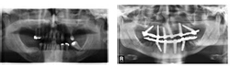

Multiple teeth dental mplants

This 48 year old woman as never been happy with a full lower denture. She is very concerned with her appearance and wants her mouth to look as good as the rest of her.

Treatment: 6 dental implants with 10 bridges over implants

Customer Speak: "This is my new life! I now have a beautiful full mouth of teeth and they are solid in my mouth and feel like my own. The appearance and form of my new teeth not only look natural, but also allow for easy cleaning. Thank you for your excellent service."